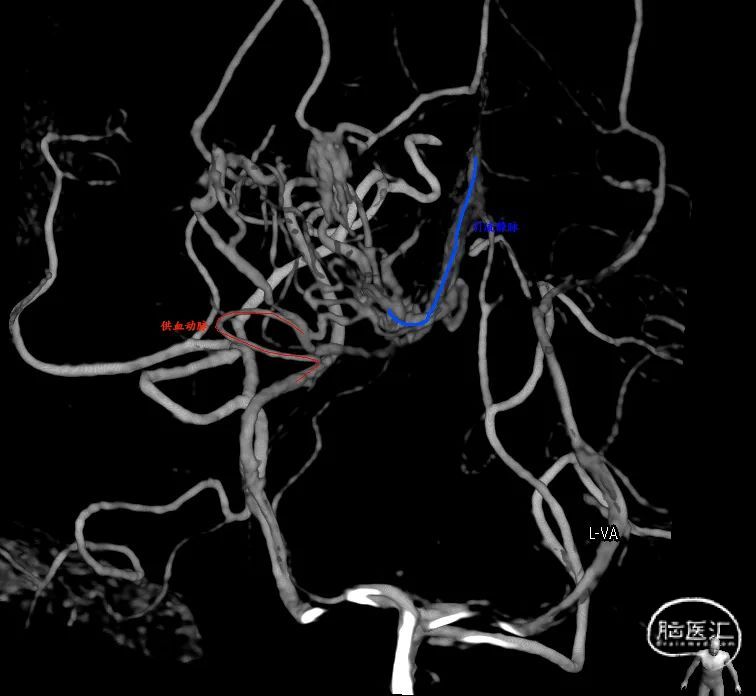

图2. DSA提示右侧脑室后角畸形血管团,由脉络膜后动脉供血。

儿童bAVM的治疗仍然很有争议,因为完全闭塞或者切除病灶并保留神经功能常常非常困难。成功的治疗往往取决于bAVM的部位和大小,以及治疗时的临床状况。总体来说手术切除是治疗破裂儿童bAVM的首选,但每个儿童接受治疗前经过神经外科医生、神经介入医生和放疗医生的多学科讨论对于治疗决策非常重要[4]。由于儿童bAVM常常位于后颅窝,比如基底节和丘脑,手术切除不利于神经功能的保留。近些年神经介入从材料和技术都有了很大的发展,性能更好的微导管和微导丝能够超选到更小的供血动脉或者引流静脉;头端可解脱微导管降低了栓塞剂粘管的风险;多种新的液体栓塞剂包括NBCA胶和Onyx胶的应用,尤其是Onyx胶大大提高了介入治疗bAVM的治愈率[5];高压锅技术的推广等等[6]。本例患者为单一供血和单一静脉静脉引流,采取了经动脉途径栓塞,为了使栓塞剂更容易弥散至畸形团,将NBCA胶水做了较大程度的稀释。经动脉途径栓塞治疗bAVM的缺点是全完栓塞率较低,因此需要密切影像学随访,必要时可以选择二次经静脉途径栓塞或者采取局部放射治疗[4]。本例患者术后恢复良好,但仍需影像学密切随访。此外对于大型复杂的bAVM可以采取介入栓塞治疗危险靶点栓塞比如血流相关动脉瘤、动静脉瘘或者畸形团内严重扩张的静脉结构,能够降低bAVM再出血和保留患者的重要神经功能[7]。